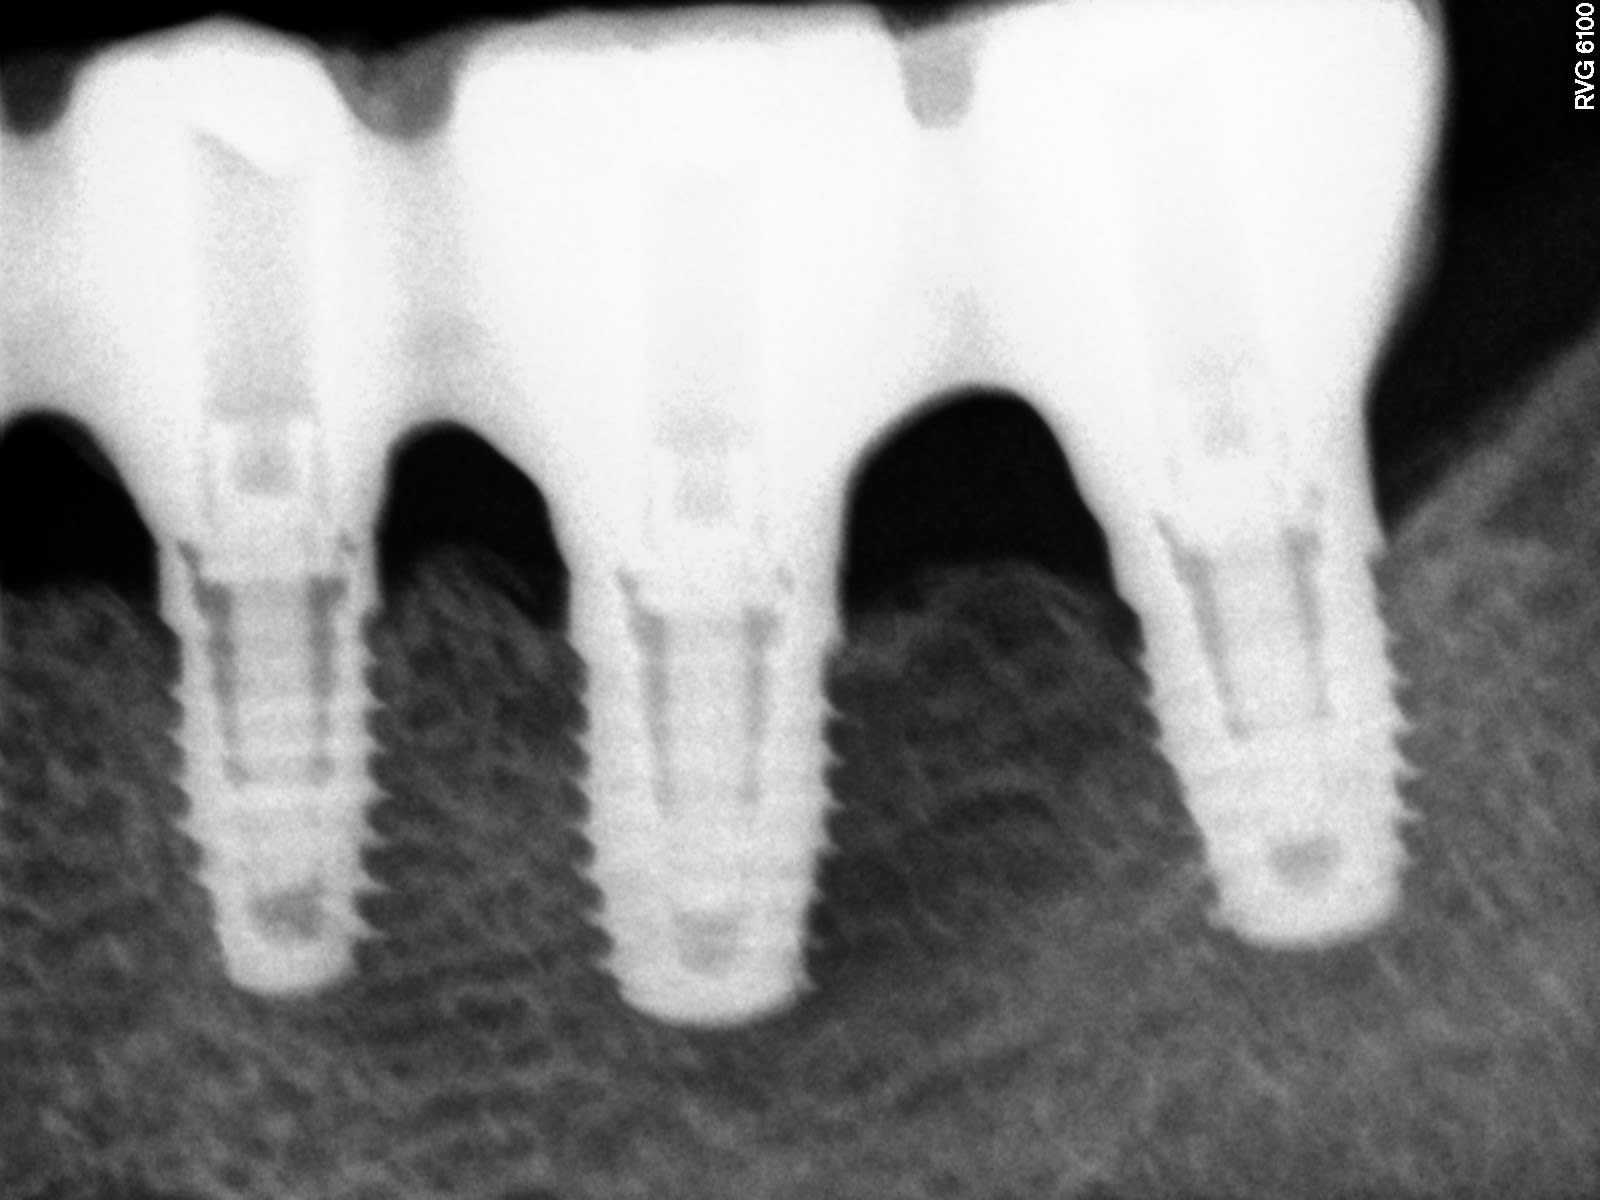

et bien ce que je trouve de plus ressemblant, c'est çà

http://osseosource.com/dental-implants/product_info.php?products_id=2004

mais vraiment pas convaincu: ce qui me trouble, c'est la longueur de la vis de prothèse dans l'implant....

donc je continue mes recherches....